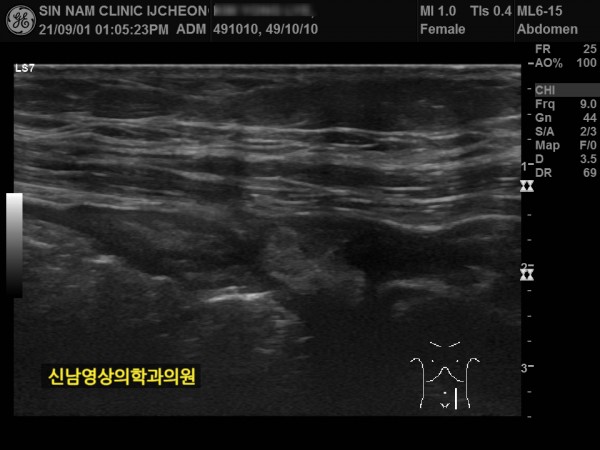

본 환자분께서는 사흘 정도 지속되는 복통과 고열로 내원하신 60대 중반의 환자분입니다.

복통 부위의 병변을 확인하기 위해서 복부 촬영과 복부 초음파검사를 진행했고, 맹장은 이상이 없고, 대장 주위로 복강삼출액(물)이 둘러싸고 있으면서 상행대장부위의 부종이 심하게 발견되었습니다.

원내 피검사상 백혈구 수치가 높아 대학병원 응급실로 전원 조치하고 응급수술을 받으셨고...